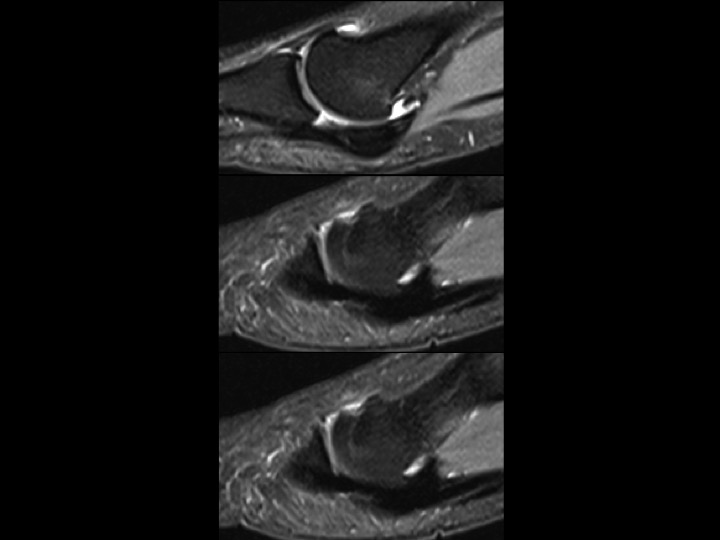

31F 5 years pain, evaluate sesamoid AVN

In the AP XR, the fibular sesamoid is not visible, but in the sesamoid view, its diminutive, smooth and not sclerotic. This leads me to believe that this is marked hypoplasia rather than AVN. Hallucal sesamoid variants are common. Aplasia is uncommon. Hypoplasia is not rare, but this degree of hypoplasia seems unusual. Based on the images, it seems there is compensatory thickening of the fibular portion of the plantar plate (sesamoids are embedded in the plantar plate). Structures stay where they are supposed to be: the tibial sesamoid is located and the FHL is midline in the short axis image. Shes had pain for 5 years....which I cannot explain, other than to say that normal variants may be symptomatic. The attached article is a little crazy, check it out. Reference article.